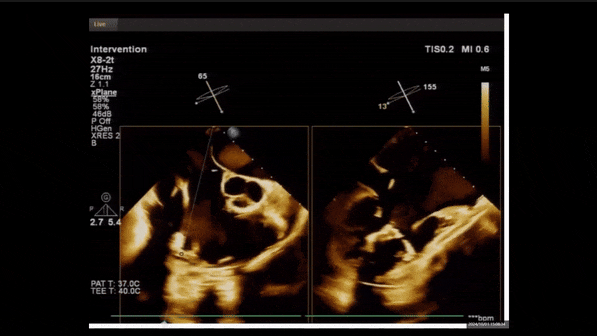

術(shù)前TEE評估

1、3D TEE顯示雙房及右室擴(kuò)大,右室中段直徑40mm,右室FCA 52%。三尖瓣環(huán)TAPSE 22mm,三尖瓣環(huán)左右徑49mm,三尖瓣隔葉長度16mm,前葉長度21mm,后葉長度34mm,三尖瓣前隔gap 11mm,后隔gap 5.6mm,AP gap 12mm,診斷極重度功能性三尖瓣返流(Type I型三尖瓣:Torrential FTR 5+)。

2、彩色多普勒顯示:收縮期三尖瓣口返流束起源于后隔交界、前后葉之間及前隔交界,返流束縮流頸最大寬度27mm,三尖瓣返流口EOA=2.02cm2,返流容積124ml,收縮期三尖瓣返流峰值速度2.64m/s,返流峰值壓差28mmHg,PAPs 43mmHg,舒張期三尖瓣口平均跨瓣壓差1mmHg,肝左靜脈可見明顯逆向血流波。

術(shù)中經(jīng)食道超聲輔助下可見LuX-Valve Plus夾持件抓捕瓣葉狀態(tài)良好,夾持件在位,室間隔錨定位置良好,假體瓣膜整體錨定狀態(tài)穩(wěn)固。

術(shù)后三維超聲

術(shù)后即刻經(jīng)食道超聲可見,三尖瓣假體瓣膜位置合適,牛心包瓣葉運(yùn)動狀態(tài)良好,開閉正常,瓣周及瓣葉對合緣處未見明顯返流,心電圖及心包狀態(tài)較術(shù)前無明顯變化。